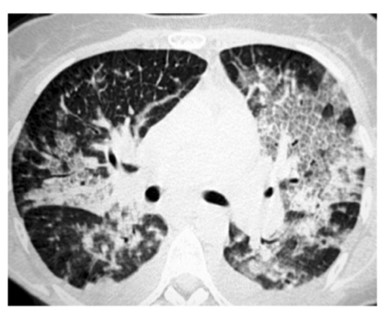

Spontaneous pneumothorax is a common clinical condition in respiratory medicine, typically managed through either conservative measures or pleural drainage. One of the recognized complications following drainage is re-expansion pulmonary edema (REPE), which is usually mild and self-limiting. However, in rare instances, REPE can manifest severely. This report describes a case of unilateral severe REPE that developed shortly after pleural drainage for a spontaneous pneumothorax, complicated by extensive pulmonary plasma leakage. The patient experienced a sudden and critical decline in both respiratory and circulatory status. Emergency management included prone and head-down positioning to optimize ventilationperfusion matching, aggressive fluid resuscitation, and initiation of mechanical ventilation. This clinical course highlights the potential for REPE to progress rapidly to life-threatening respiratory and hemodynamic failure. Clinicians should maintain a high index of suspicion for severe pulmonary re-expansion edema in patients who deteriorate shortly after seemingly successful pleural decompression. Early recognition and supportive interventions are vital for improving outcomes in such critical presentations. In this case report, we discuss such a challenging case, its management and further course we learnt to support our readers.